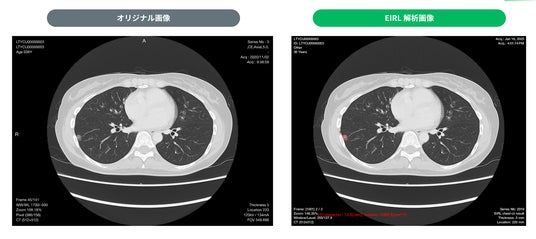

・検出例

2. 17.4mm 部分充実型